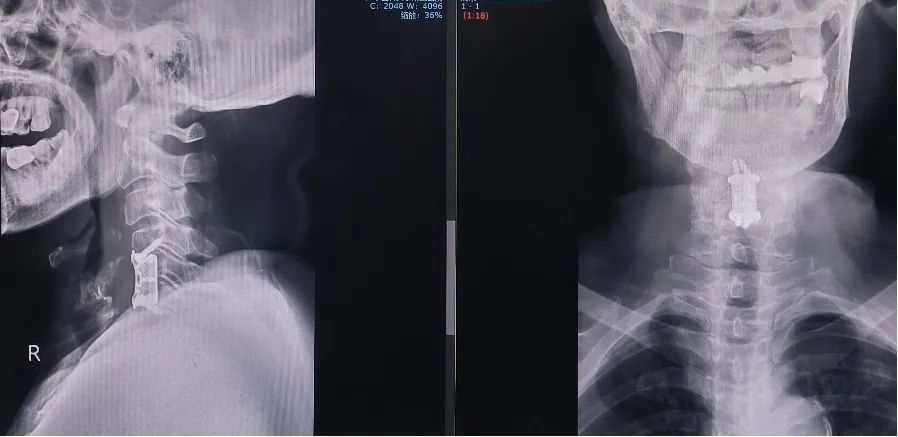

术后,患者恢复良好,四肢麻木感明显减轻,逐渐感觉手部力量明显改善。手术取得成功,不仅解除了病痛,也为其生活质量带来了实质性的提升,休息一段时间,何女士又可以恢复正常生活了。何女士表示,通过这次手术,我不仅摆脱了长期困扰的病痛,也深深感受到了医院的专业水准和服务态度,我非常感谢这里的医生们给我带来的新生。魏劲松主任嘱托患者注意复查和康复锻炼,并表示将继续发挥该科室在脊柱疾病治疗领域的优势,为更多患有类似疾病的患者解决病痛,保驾护航。

术后复查